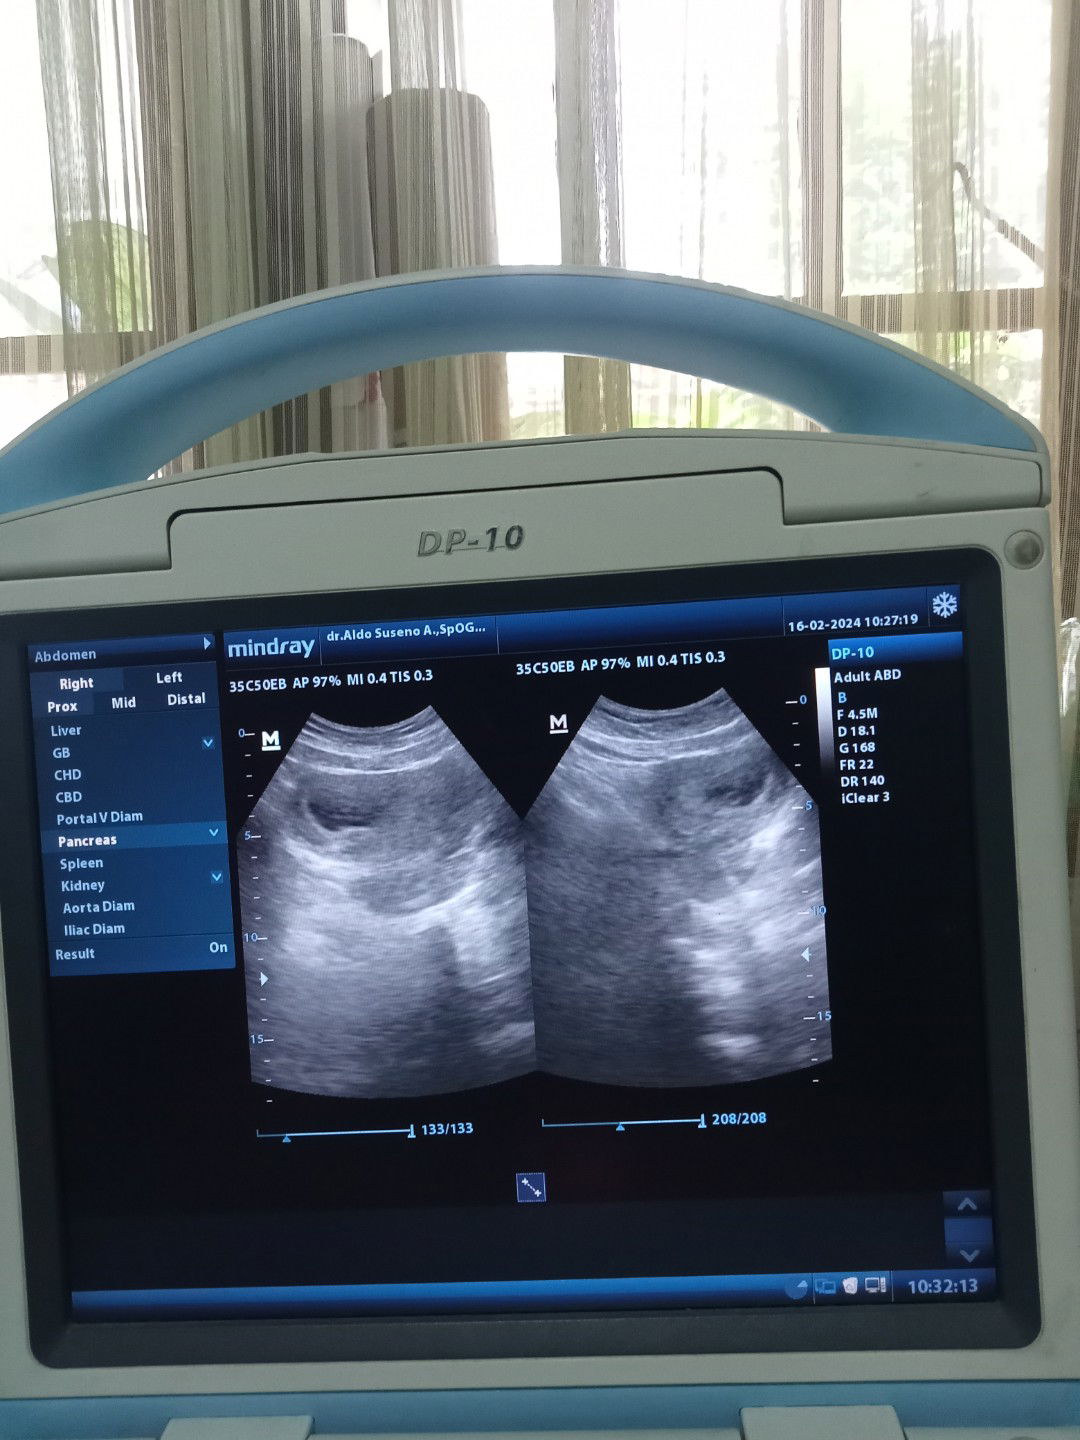

Hamil 9 minggu

Hamil 9 minggu baru ada kantung aja normal gk bun?

9 minggu menurut hpht atau menurut ukuran GS saat USG? Soalnya saya pertama kali USG harusnya 8weeks, tapi kata dokter baru 7weeks dilihat dari ukuran kantung janinnya, dan belum ada janin dan djj. Kalau kata obgyn saya sih gapapa, karena ukuran kantung janinnya bagus. Dokter saya pun bukan tipe yang langsung bilang hamil BO saat usia kehamilan 9weeks tapi belum ada janin. Makanya saya malah disuruh baliknya 2 bulan lagi aja gapapa.